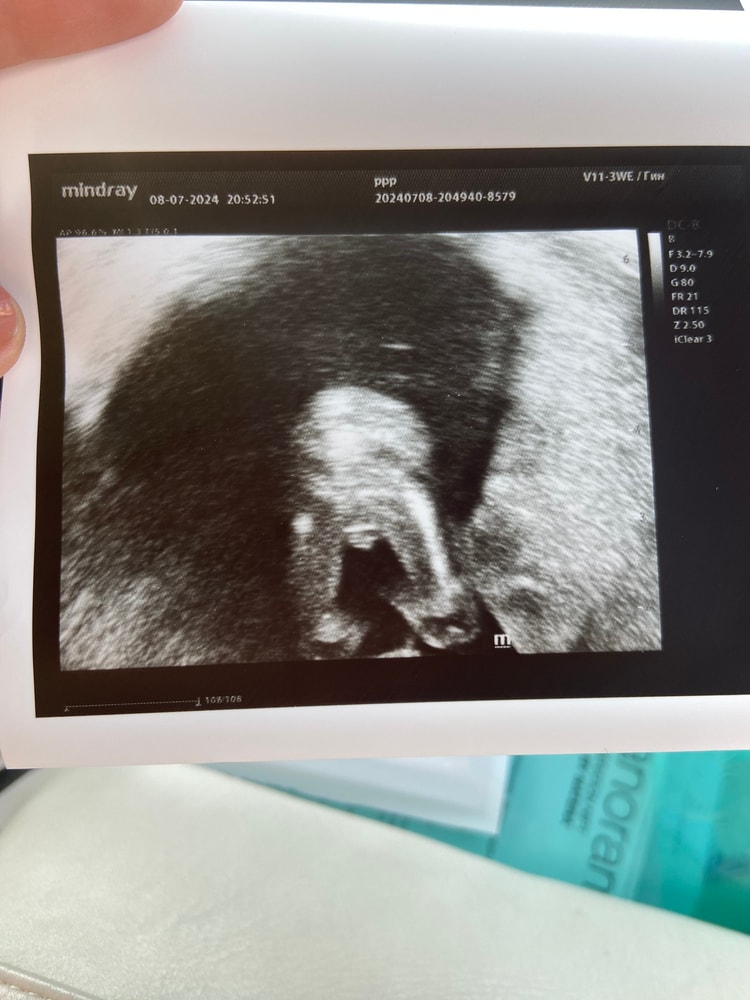

УЗИ 17+3 недели

Пол малышаВсём привет. Ходили сегодня на УЗИ нам показали сыночка, врач подтвердил сказал что уже точно не чего не отвалиться😀

Но всё равно какой то червь сомнения есть. Так как говорят некоторые что на этом сроке у всех похоже. Интересно ваше мнение)

Вот 14 недель узи, сын)

И у Вас такая же картинка 😄